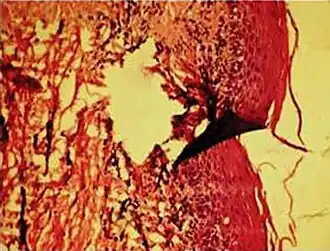

In microscopy, an artifact is an apparent structural detail that is caused by the processing of the specimen and is thus not a legitimate feature of the specimen. In light microscopy, artifacts may be produced by air bubbles trapped under the slide's cover slip.[1]

In electron microscopy, distortions may be produced in the drying out of the specimen. Staining can cause the appearance of solid chemical deposits that may be seen as structures inside the cell. Different techniques including freeze-fracturing and cell fractionation may be used to overcome the problems of artifacts.[1]

A crush artifact is an artificial elongation and distortion seen in histopathology and cytopathology studies, presumably because of iatrogenic compression of tissues. Distortion can be caused by the slightest compression of tissue and can provide difficulties in diagnosis.[2][3] It may cause chromatin to be squeezed out of nuclei.[4] Inflammatory and tumor cells are most susceptible to crush artifacts.[4]